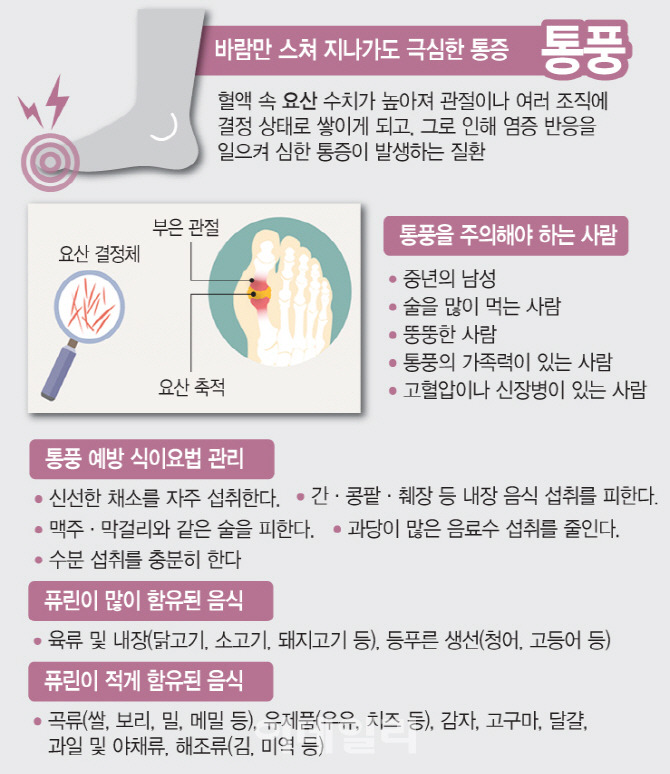

통풍(Gout)

우리가 흔히 먹는 고기나 술에는 퓨린이란 물질이 많이 들어 있습니다.

요산이란 우리가 먹는 여러 음식이 소화되어 최종적으로 대사된 후 나오는 물질로서

보통 혈액 내에 녹아 있다가 소변으로 배출됩니다.

통풍 환자에서는 혈액 내 요산이 지나치게 많아서 이것이 결정체로 변하고,

이 요산 결정체가 관절 내에 침착하여 염증을 유발하게 되는 것입니다.

대개의 통풍 환자들은 혈액 내에 요산이 정상치 이상으로 높은,

소위 고요산혈증을 가지고 있습니다. 하지만 아무 증상 없이 고요산혈증을 가진 사람들이

훨씬 더 많기 때문에 요산이 높다고 모두 통풍 환자가 되는 것은 절대 아닙니다.

통풍 관절염은 고요산혈증이 심할수록, 또 기간이 오래될수록 발병할 가능성이 높아집니다.

통풍 환자는 거의 남자이고 대개 첫 발작적 관절염을 40~50세에서 경험합니다.

한때 통풍은 좋은 음식을 먹고 술 마시는 부유층의 병으로 간주되기도 했지만

요즘은 식생활이 윤택해지면서 사회계층에 관계없이 발생합니다.

물론 식생활 습관이나 음주가 통풍 발병에 중요한 것은 아직도 사실입니다.

통풍은 식습관과 비만 때문에 생기는 경우가 많기 때문에 식생활 개선이 필요합니다.